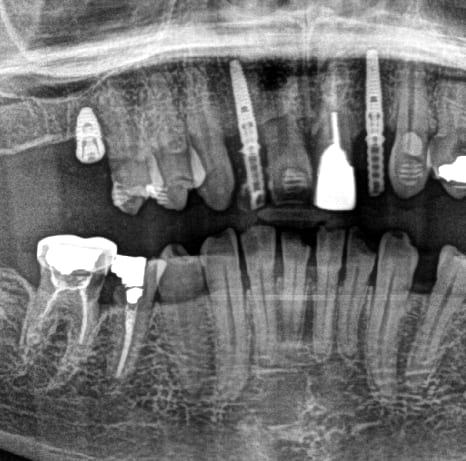

Bonjour à tous. Sauriez-vous me dire de quel type d'implant s'agit-il ?

rétroalvéolaires stp

identification= rétro, une pano c'est trop imprécis (pas assez de détails)

C'est un bon coup de tourne à gauche qu'il faut pour cet implant "bone level" à moitié enfoui.

Je ne m'amuserais pas à faire la prothèse sur un implant en survie...